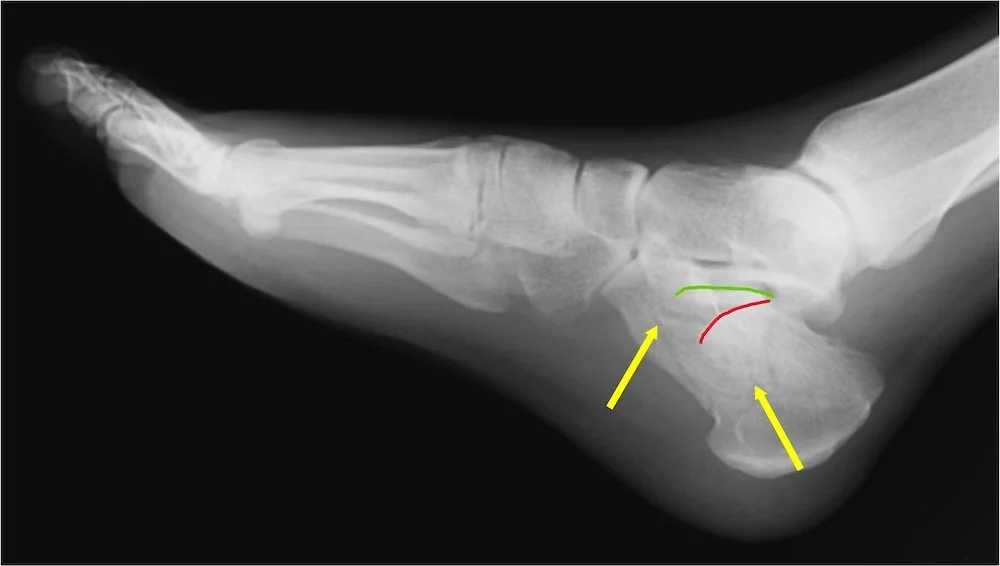

The first picture is what is called a joint depression fracture. the body weight lands hard on the foot and crushes the joint pushing the cartilage down into the actual interior of the heel bone. The yellow arrows show fracture lines, there are many fracture peices in this case. The red curved line shows the position of the subtalar joint that is displaced downward, forced there by the body weight. The green curved line shows where it used to be before is was crushed down.